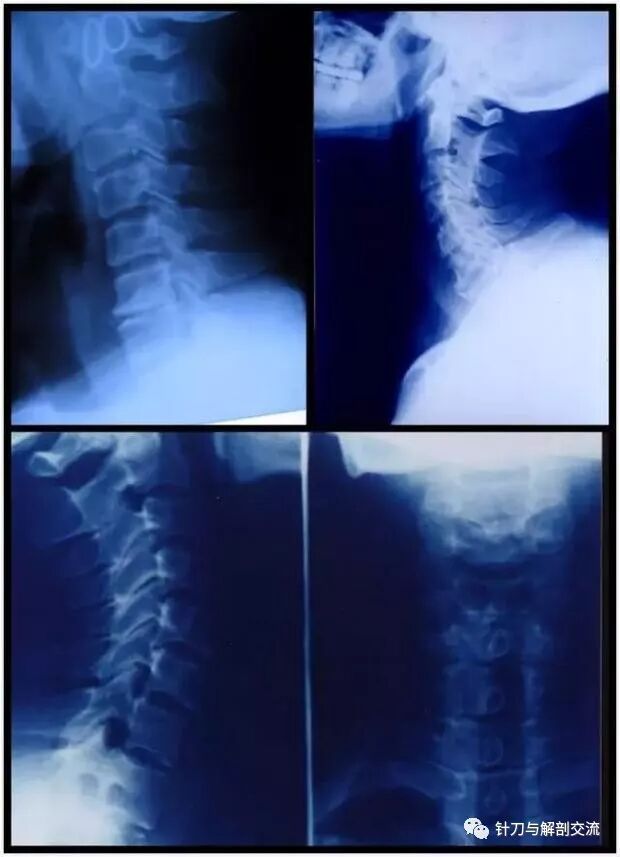

颈椎X线上可以看到:生理曲度变直、颈椎序列不齐、颈椎失稳、椎间隙变窄,椎体前缘增生,骨桥形成。

3、颈椎X线检查:常规拍摄颈椎正、侧、开口位X线 片,必要时加照颈椎左、右斜位及过伸、过屈位片有上述表现者;